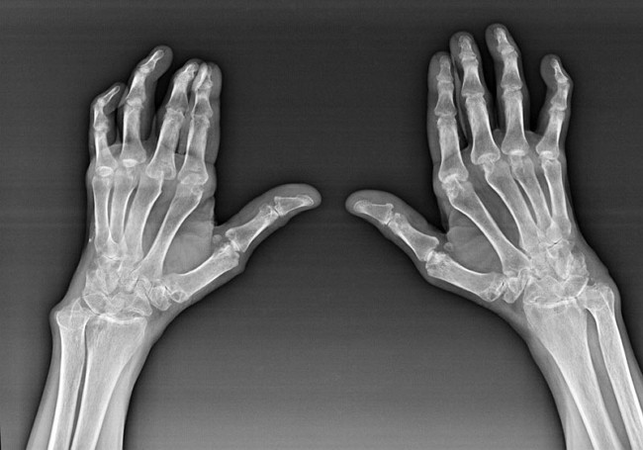

Despite the fact that rheumatoid arthritis is a systemic disease under it, to a greater extent, the joints suffer, while the lesion of other tissues and organs is in the background.With this disease, almost all types of brush joints can be affected (wristwalls, carpal-paths, metacarpal-phalanx, inter-phalanx joints).The lesion is usually symmetrical (those.The same joints are affected) on both hands, accompanied by swelling, pain in damaged joints.In the morning, during lifting from bed, there is some stiffness in the affected joints, which can last about 1 hour and then disappear without a trace.

Quite often with rheumatic arthritis near the affected joints of the brush (more often the piano-phalanx, inter-phalanx joints) Rheumatoid nodules appear.They are a rounded formation located under the skin.On the brush, these formations arise most often on the back.On palpation, they are dense, inactive, painless.The number of them can vary.